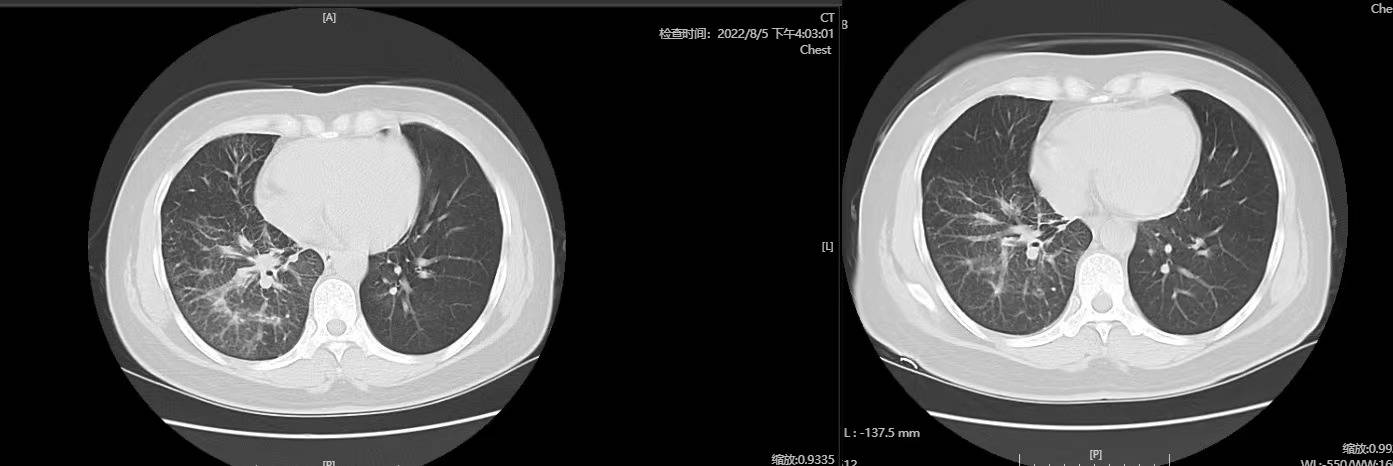

(左边8月,右边7月)

癌性淋巴管炎真的是,太难了。